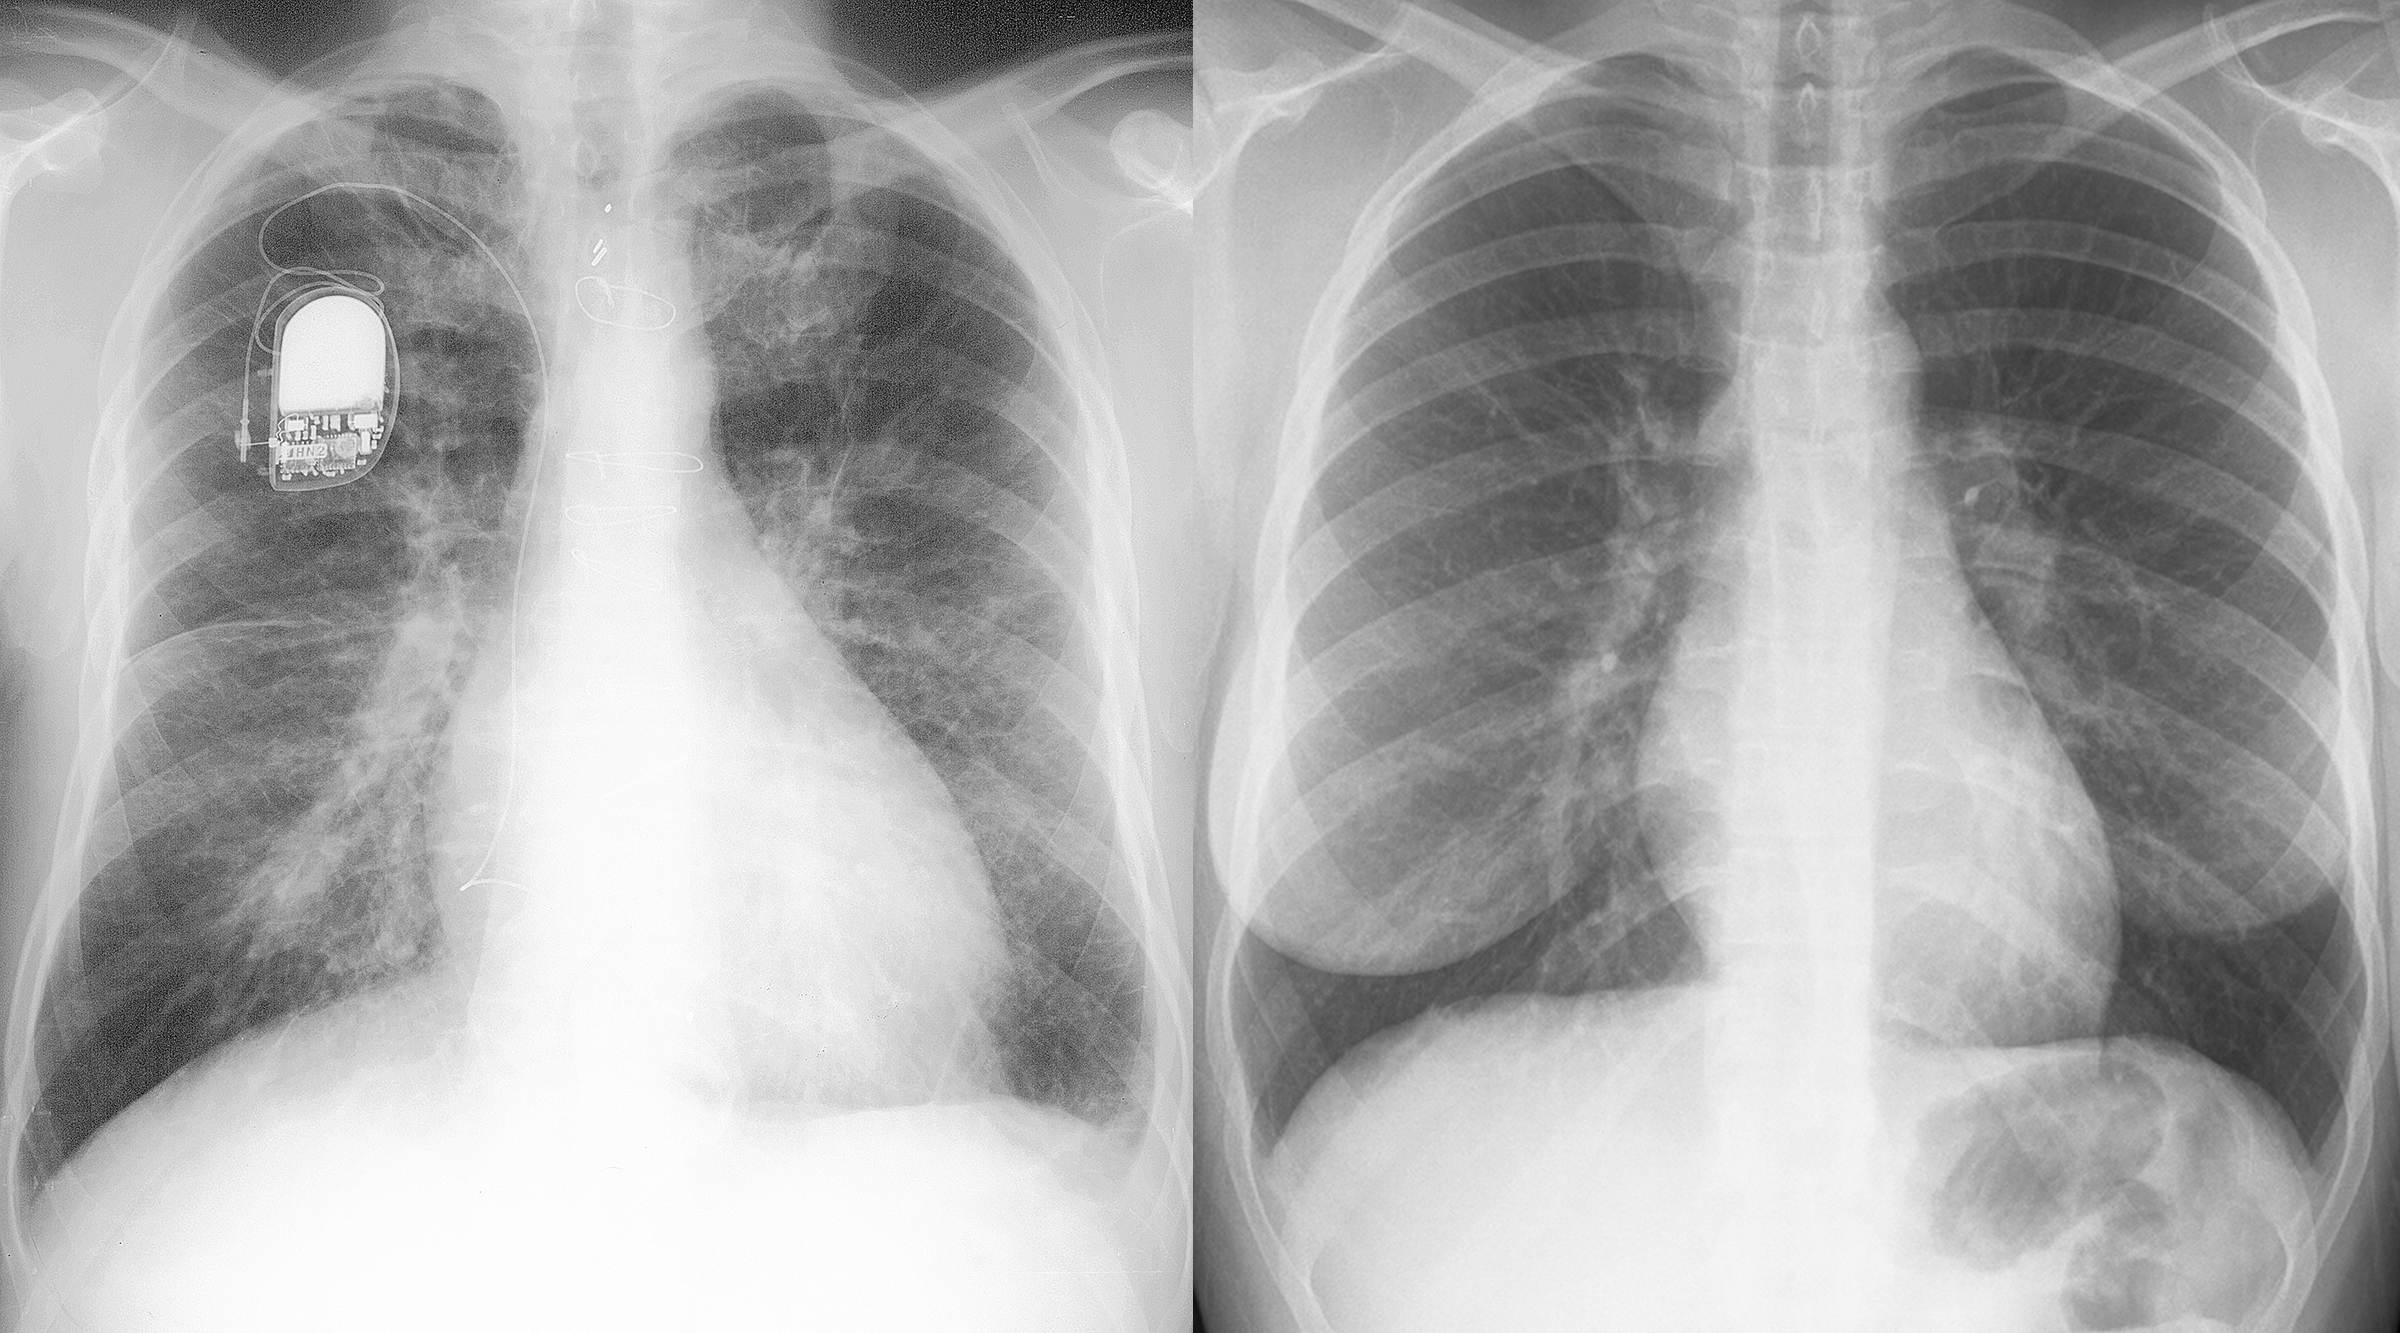

◂Chest CT for Internal Medicine Residents